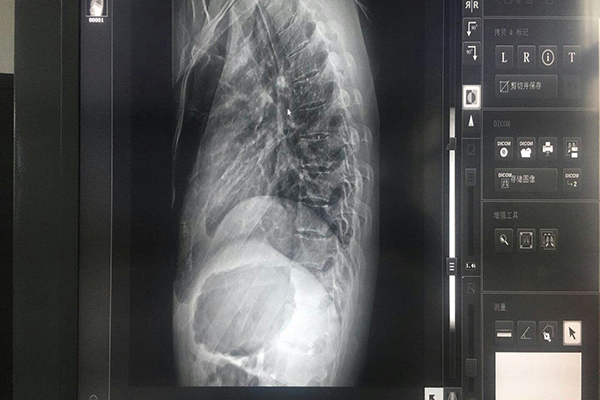

顯示器校準,嚴格講應該是通過“顯示鏈路”對顯示器的“顯示效果”進行校準。其目的,是保持數(shù)字影像顯示的標準性和一致性。校準的對象,主要是顯示器上各個像素的亮度值(一般用ftL即英尺流明數(shù)),其次是空間畸變(如畫一直線結果顯示成一曲線、畫一正方形結果顯示一長方形或梯形)。醫(yī)用顯示器區(qū)別于普通顯示器的重點是亮度值的校準。

亮度值主要校準三個值:至大亮度值、至小亮度值、線性度。參數(shù)性能上要滿足上面這些要求,生產(chǎn)量大概不到普通顯示器的百萬分之一,醫(yī)用顯示器的價格能不昂貴嗎?醫(yī)用顯示器的選購配置成了醫(yī)院和PACS集成商關注的焦點,了解醫(yī)用顯示器與普通顯示器在技術性能和質(zhì)量的差別,根據(jù)本單位的具體情況,搭配不同類型、不同檔次顯示器,在滿足影像質(zhì)量前提下節(jié)約醫(yī)院資金,體現(xiàn)合理性與經(jīng)濟性。